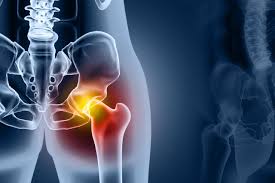

고관절 치환술(인공관절 수술)

심한 관절염이나 괴사로 기능이 상실된 경우 인공관절로 대체합니다.